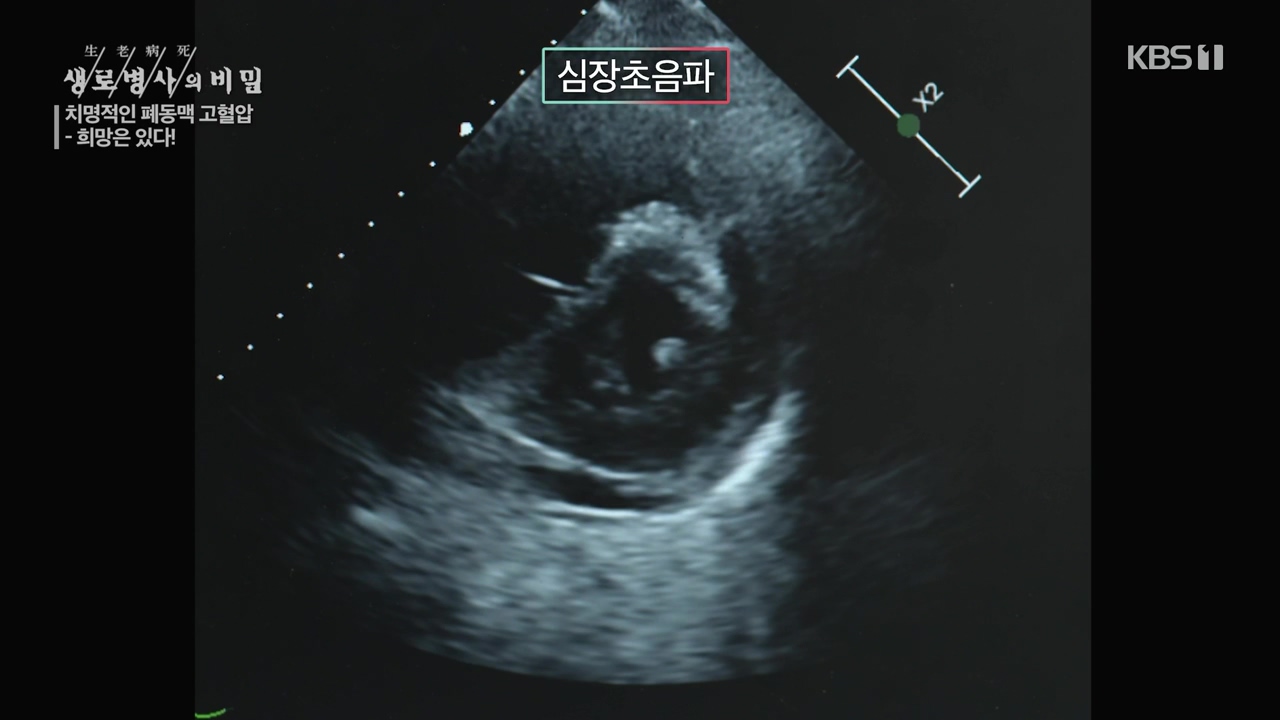

생로병사의 비밀, 이유없이 숨이 찬 증상이 오래간다면...세상에서 가장 슬픈 병 '폐동맥 고혈압' 생존율 높인 최신 약제 방송을 보고나서.

[한국강사신문 이미숙 기자] 폐동맥이 두꺼워져 심장과 폐순환의 압력이 높아지는 폐동맥 고혈압! 폐동맥 고혈압은 과거, 쓸 수 있는 약이 없어 진단...